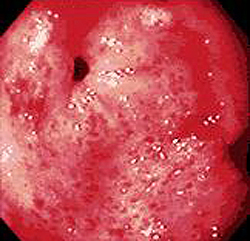

- Эндоскопия желудка. Ключевым методом диагностики заболевания является эзофагогастродуоденоскопия с биопсией слизистой оболочки. При исследовании обнаруживают повышенное выделение слизи, гиперемию и отечность слизистой. Зачастую подобные изменения имеются и в двенадцатиперстной кишке. Иногда в желудке может визуализироваться желчь, что является следствием дуодено-гастрального рефлюкса.

- Биопсия. Для окончательного подтверждения диагноза используется эндоскопическая биопсия, при которой в гистологическом материале обнаруживают признаки поверхностного воспаления в виде лимфо-плазмоцитарной инфильтрации слизистой оболочки. По современным рекомендациям биоптат берется из антрального и фундального отделов желудка. При хроническом поверхностном гастрите патологический процесс чаще всего локализуется в антральном отделе.